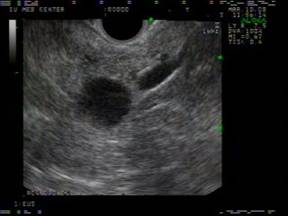

The EUS appearance of mucinous cystic neoplasm is variable. They are commonly associated with a visible wall and septations of variable thickness, and peripheral calcifications can be seen in some cases (Figures 1 and 2) [43]. Invasive malignancy has been associated with the presence of thick or irregular cyst wall, intramural nodules or solid components and larger cyst size (Figure 3) [14]. EUS-FNA cytology could reveal columnar epithelial cells in up to half of the patients in association with extracellular mucin [34, 46]. Mucin is frequently identified on EUS-FNA of mucinous cystic neoplasm and cyst fluid is typically clear with elevated CEA levels and low amylase. Mucinous cystic neoplasms are premalignant lesions but the risk of malignant degeneration is likely less than that of IPMN [45]. The risk of malignancy in these tumors described in a series of 163 patients was found to be 17.5% [47]. Therefore, surgical resection is recommended for all surgically fit patients. The prognosis after surgery for mucinous cystic neoplasm that have not undergone malignant transformation is excellent and the 5-year survival for mucinous cystadenocarcinomas post resection exceeds 60% [6, 48].

Figure 1. EUS findings in a 42-year-old female patient with a mucinous cystic neoplasm in the body of the pancreas. A cyst wall is present in addition to one tangential thin septum. The adjacent parenchyma appears unremarkable. No FNA was performed in this case and the patient was referred to surgery. |